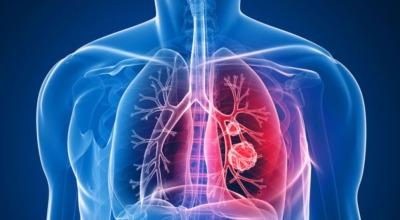

폐암은 폐에 생기는 악성 종양을 말합니다. 폐에서 직접 발생하는 원발성 폐암과, 다른 장기에서 전이되어 온 전이성 폐암으로 나눌 수 있어요. 전 세계적으로 매년 약 130만 명이 폐암으로 사망하는데, 이는 암으로 인한 사망 원인 중 가장 높은 비중을 차지하고 있습니다.

폐암 초기 증상 중 하나로 가슴 통증이 있습니다. 폐암 환자의 약 3분의 1 정도가 흉통을 호소하는데요, 이는 폐 가장자리 부분에 종양이 생기고, 그 종양이 암세포를 생성하며 흉벽과 흉막에 닿아 통증을 유발하기 때문입니다.

흉통은 여러 원인으로 발생할 수 있지만, 폐암에서 기인한 흉통은 지속적으로 쿡쿡 찌르는 듯한 느낌과 함께 가벼운 통증이 아닌 둔탁한 통증이 동반되는 경우가 많으니 주의가 필요합니다.

폐암 초기 증상 중 하나로 호흡곤란이 나타날 수 있습니다. 폐암 환자의 약 50%가 숨이 차다고 느낀다고 알려져 있어요. 이는 암 덩어리가 커져 숨이 가빠지는 경우도 있지만, 폐암으로 인한 폐 허탈, 상기도 폐색, 흉막 삼출 등이 호흡곤란을 일으키기도 합니다. 평소와 달리 숨이 차고, 숨을 들이쉬거나 내쉴 때 쌕쌕거리는 소리가 난다면 폐암 초기 증상을 의심해 볼 필요가 있습니다.